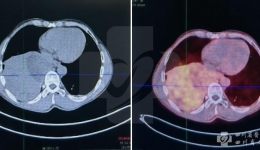

• 罕见!频发严重低血糖,竟是因为胸部这个包块!

罕见!频发严重低血糖,竟是因为胸部这个包块!

今年4月,一名来自西藏地区的54岁男性患者,因为“反复昏睡、抽搐、大汗7月,加重1月”入院。7个月以来,患者反复出现昏睡、意识不清、肌肉抽搐、四肢僵硬,伴大汗、不自觉吼叫。到当地医院住院时监测昏睡中血糖仅有1~2mmol/L,脑CT未见明显异常,...